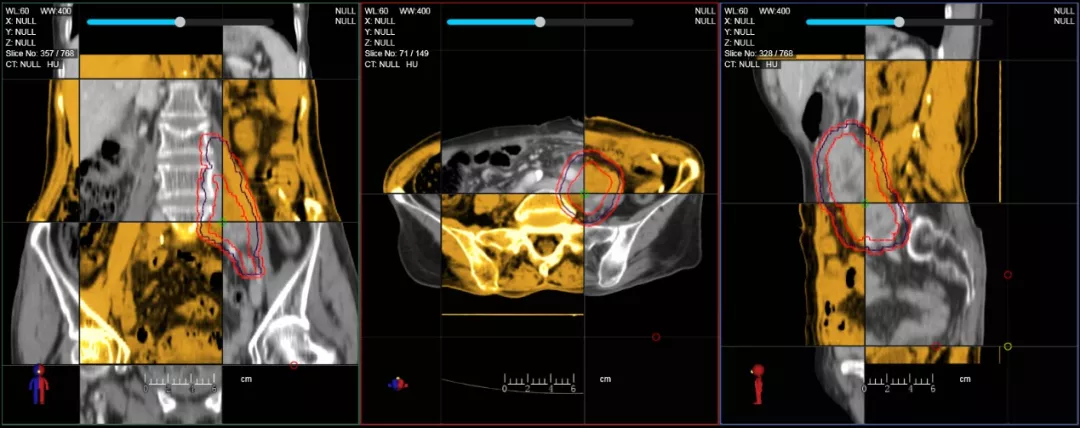

一體化CT-linac讓自適應(yīng)放療ART概念變?yōu)楝F(xiàn)實(shí)?;颊呷煶虪顟B(tài)監(jiān)控,適時(shí)在線調(diào)整治療計(jì)劃,精準(zhǔn)控制治療劑量,為患者動(dòng)態(tài)定制個(gè)體化治療方案。uAI賦能智能勾畫和自動(dòng)計(jì)劃,秒級(jí)勾勒靶區(qū)和危及器官,大幅縮短自適應(yīng)放療時(shí)間。

在線自適應(yīng)放療流程示意圖